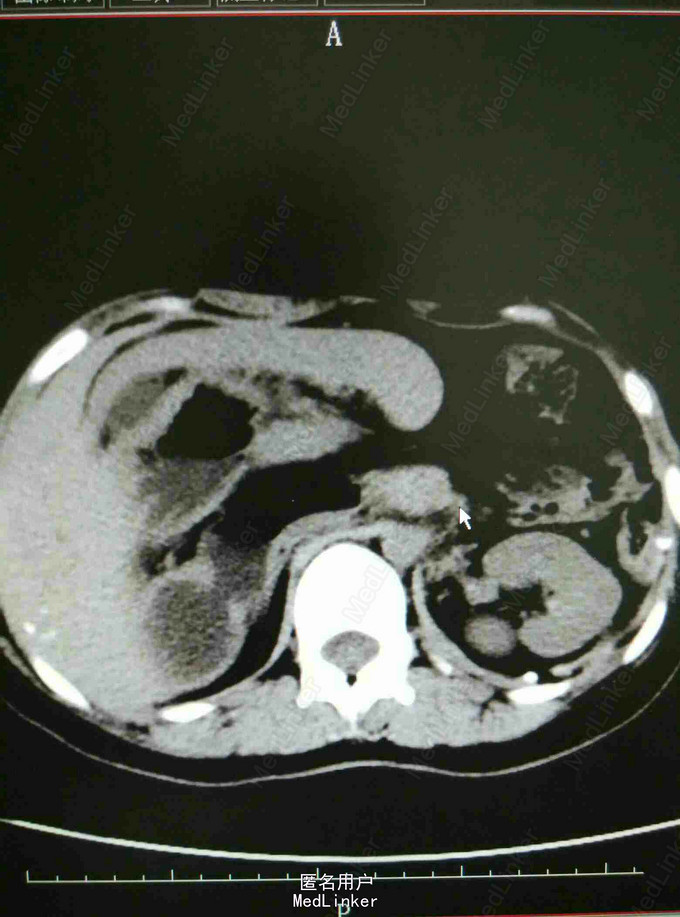

体检发现脾大一年余 患者于2014年04月体检时发现脾大、先天性膈疝。于2014年07月在中南大学湘雅医学院行胸膈疝修补术,具体术式不详,术后恢复良好。现患者为求进一步诊治入我院,门诊拟‘‘脾肿大 脾功能亢进’’收治住院。起病来,饮食睡眠可,精神良好,体重、体力无明显改变。青霉素过敏,余无特殊。

专科查体:腹平软,未见胃肠型及蠕动波,未见腹壁静脉曲张;全腹无压痛,反跳痛,肝肋下未及,胆囊未触及,右肋下脾脏可触及,Murphy征阴性;叩诊鼓音,未及移动性浊音,肠鸣音正常,肛门指检未检。入院总蛋白、白蛋白正常,白细胞2.50*10 9/L,红细胞4.36*10 12/L,血小板172*10 9/L,CT提示内脏移位,脾大,余检查无特殊。